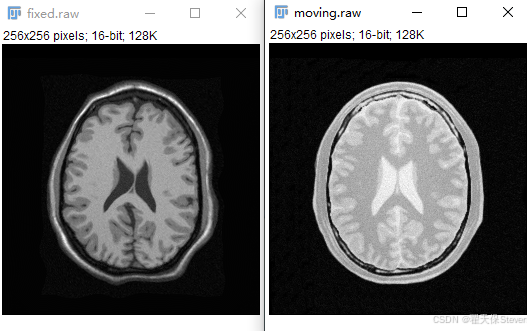

1)准备要重叠的两张图片,我这里准备了固定图像fixed.mhd和待配准图像moving.mhd。用ImageJ打开如下所示。